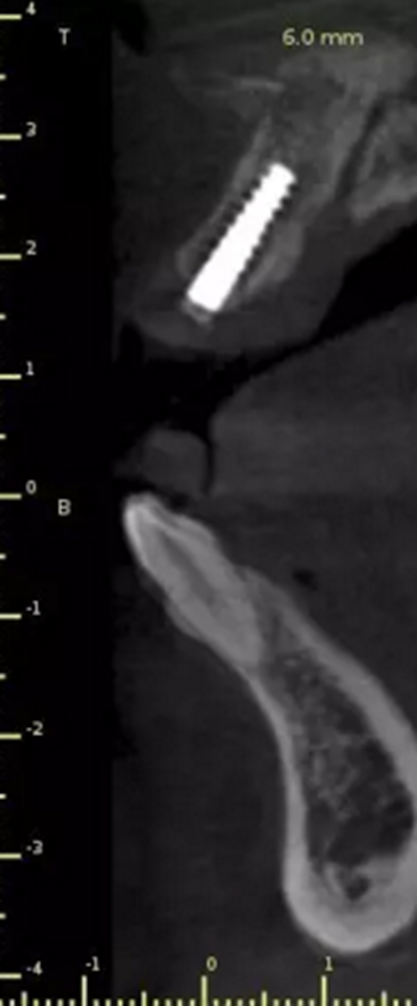

術(shù)后CT

頜面部消毒→鋪襟→局麻下翻瓣→帶入導(dǎo)板→定位鉆定位→擴(kuò)孔鉆擴(kuò)孔→植入3.0x13植體→覆蓋螺絲→縫合→沖洗→術(shù)后醫(yī)囑